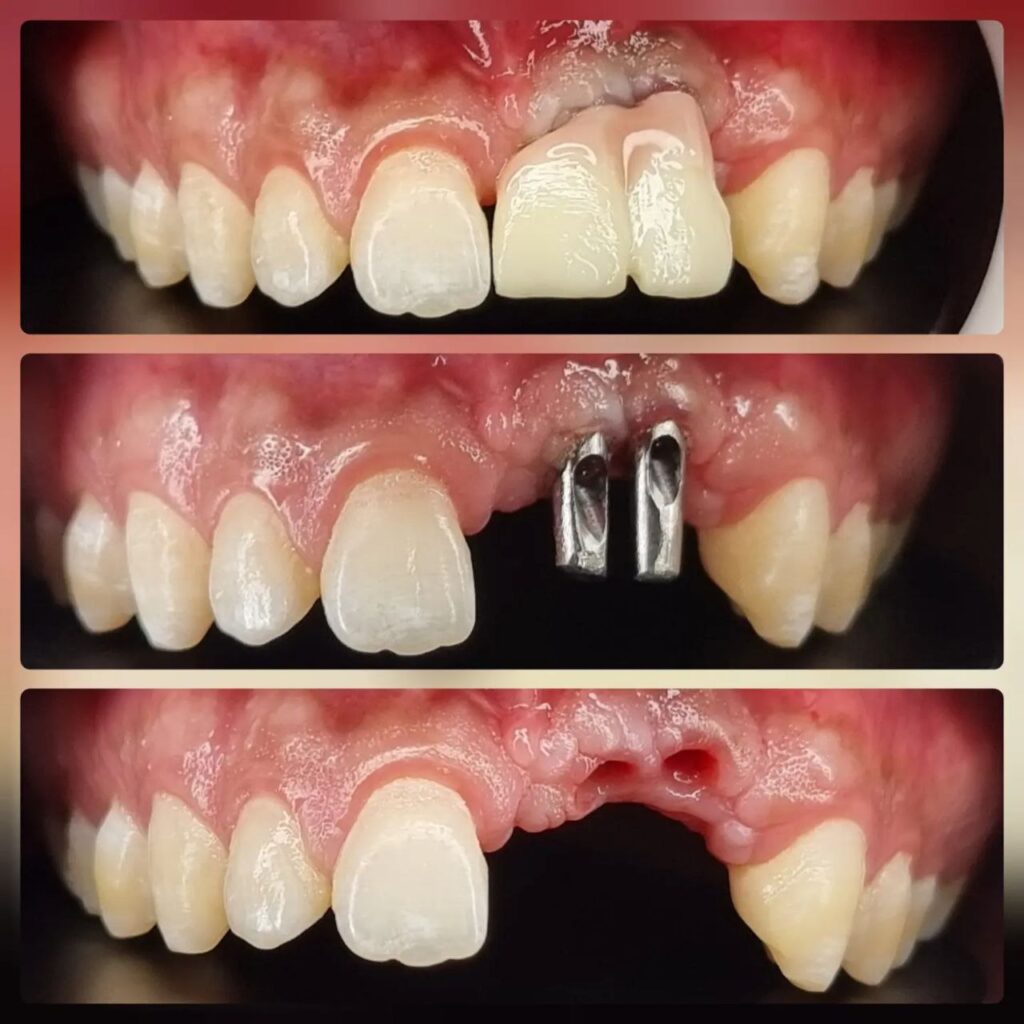

کاشت ایمپلنت دندان

اطمینان حاصل کردن از اینکه دندانهایتان به نحوی زیبا و طبیعی جایگزین شدهاند، از اهمیت بسیاری برخوردار است. ایمپلنت دندان به عنوان یک روش درمانی دائمی در دندانپزشکی شناخته میشود که حاصل آن، یک دندان زیبا و طبیعی در دهان شما خواهد بود.

هرچند که این روش درمانی هزینهی بیشتری نسبت به روشهای دیگر دارد، اما ارزش زیبایی که ایجاد میکند، قابل انکار نیست. ایمپلنتها به قدری شبیه به دندانهای طبیعی هستند که به سختی میتوان آنها را از دیگر دندانها تشخیص داد.